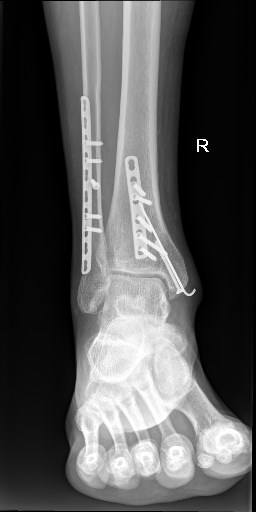

Примерно моя ситуация. В конце ноября 2023 года перелом 2 лодыжек и ББ кости.

Осенью 2024 пошел сдаваться на удаление металлоконструкций. По ДМС выбрал Пироговку на Первомайской (хирург - Ряполов). Сперва было опасение, что заднюю пластину удалить не удастся (рядом МБ нерв и сосуды), но вроде все удачно прошло, все открутилось. По времени все быстро, выписывают буквально на след день. Делали под общим ЭТН, что более щадяще для психики, чем спинальная анастезия. ![]()

После удаления по крайней мере ушли боли в районе икры при сгибании большого пальца. А вот контрактура небольшая пока осталась. Пока усиленно прохожу физиотерапию.